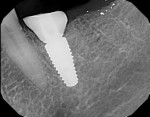

The greatest challenges in developing ideal emergence profile are choosing an implant of a proper diameter and avoiding placing the implant in too shallow of a position.24 Placing an implant too shallow or in too narrow of a space, especially in the posterior zone, will likely lead to problems as there will not be enough running room for a laboratory to sculpt the tissue (Figure 5). Conversely, an implant placed with the platform 2 mm to 3 mm apical to the CEJ of the adjacent teeth will allow for the development of a more ideal emergence profile prosthetically (Figure 6).25 Running room is defined as the distance between the implant platform and the proximal contacts with the adjacent teeth.26 The apico-coronal positioning of the implant platform should adhere to the philosophy "as shallow as possible, as deep as necessary."27 This is, in essence, a compromise between esthetics and biologic principles.

A common misconception is that emergence profile can be controlled solely through the choice of implant diameter. In the posterior zone, a large horizontal cross-section is seen with molars. A wide-diameter implant will allow for ideal emergence profile, as it closely resembles the profile of the natural tooth at the CEJ level. A wide-diameter implant may be used assuming there is at least 2 mm of buccal and lingual thickness remaining after placement.28 Alternatively, a narrower implant may be chosen with subcrestal placement to allow for appropriate vertical room for emergence profile development. Clinicians should check with each dental implant manufacturer's recommendations and know the titanium grade to ensure that the implant can support the occlusal load of the site where the replacement is occurring.29,30 Patient parafunctional habits and bone density by zone of mouth also need to be critically examined to ensure long-term success without overload.31